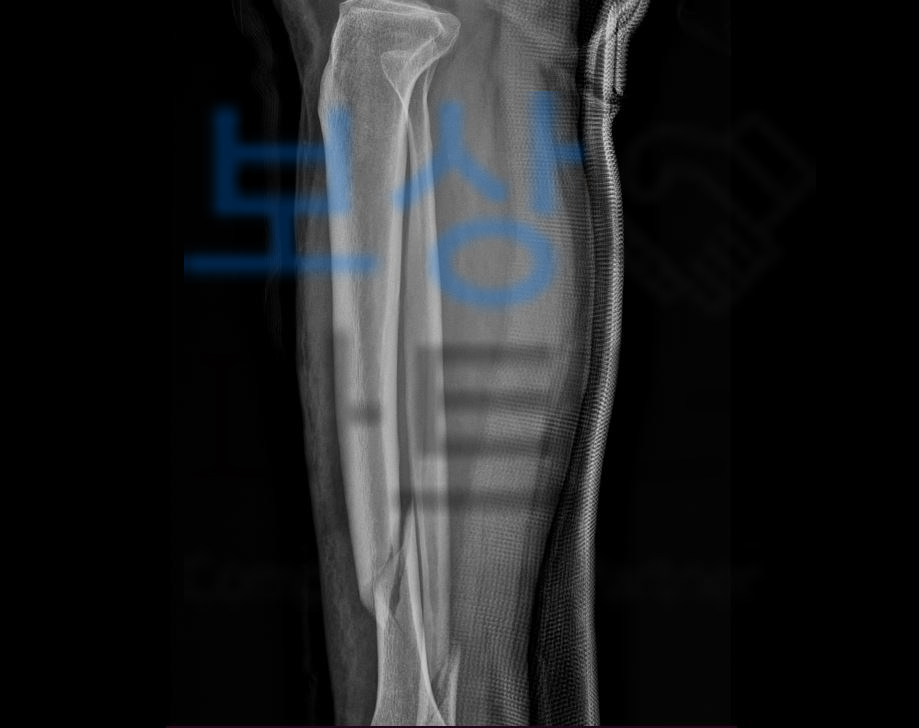

김@@님은 넘어지면서 다리를 다치는 사고를 당하셨는데요,

기록지 상의 tibia 즉 경골의 골절이 심각했고 정밀검사를 받아 보니…

위처럼 골절의 정도가 심각하여 금속으로 고정하여야 하였습니다. 골절진단비, 실비, 수술비는 보험사에서 요청하는 대로 진단서나 영수증을 받아 청구하시기만 해도 받으십니다. 하지만 저희가 소개해드릴 보험금은